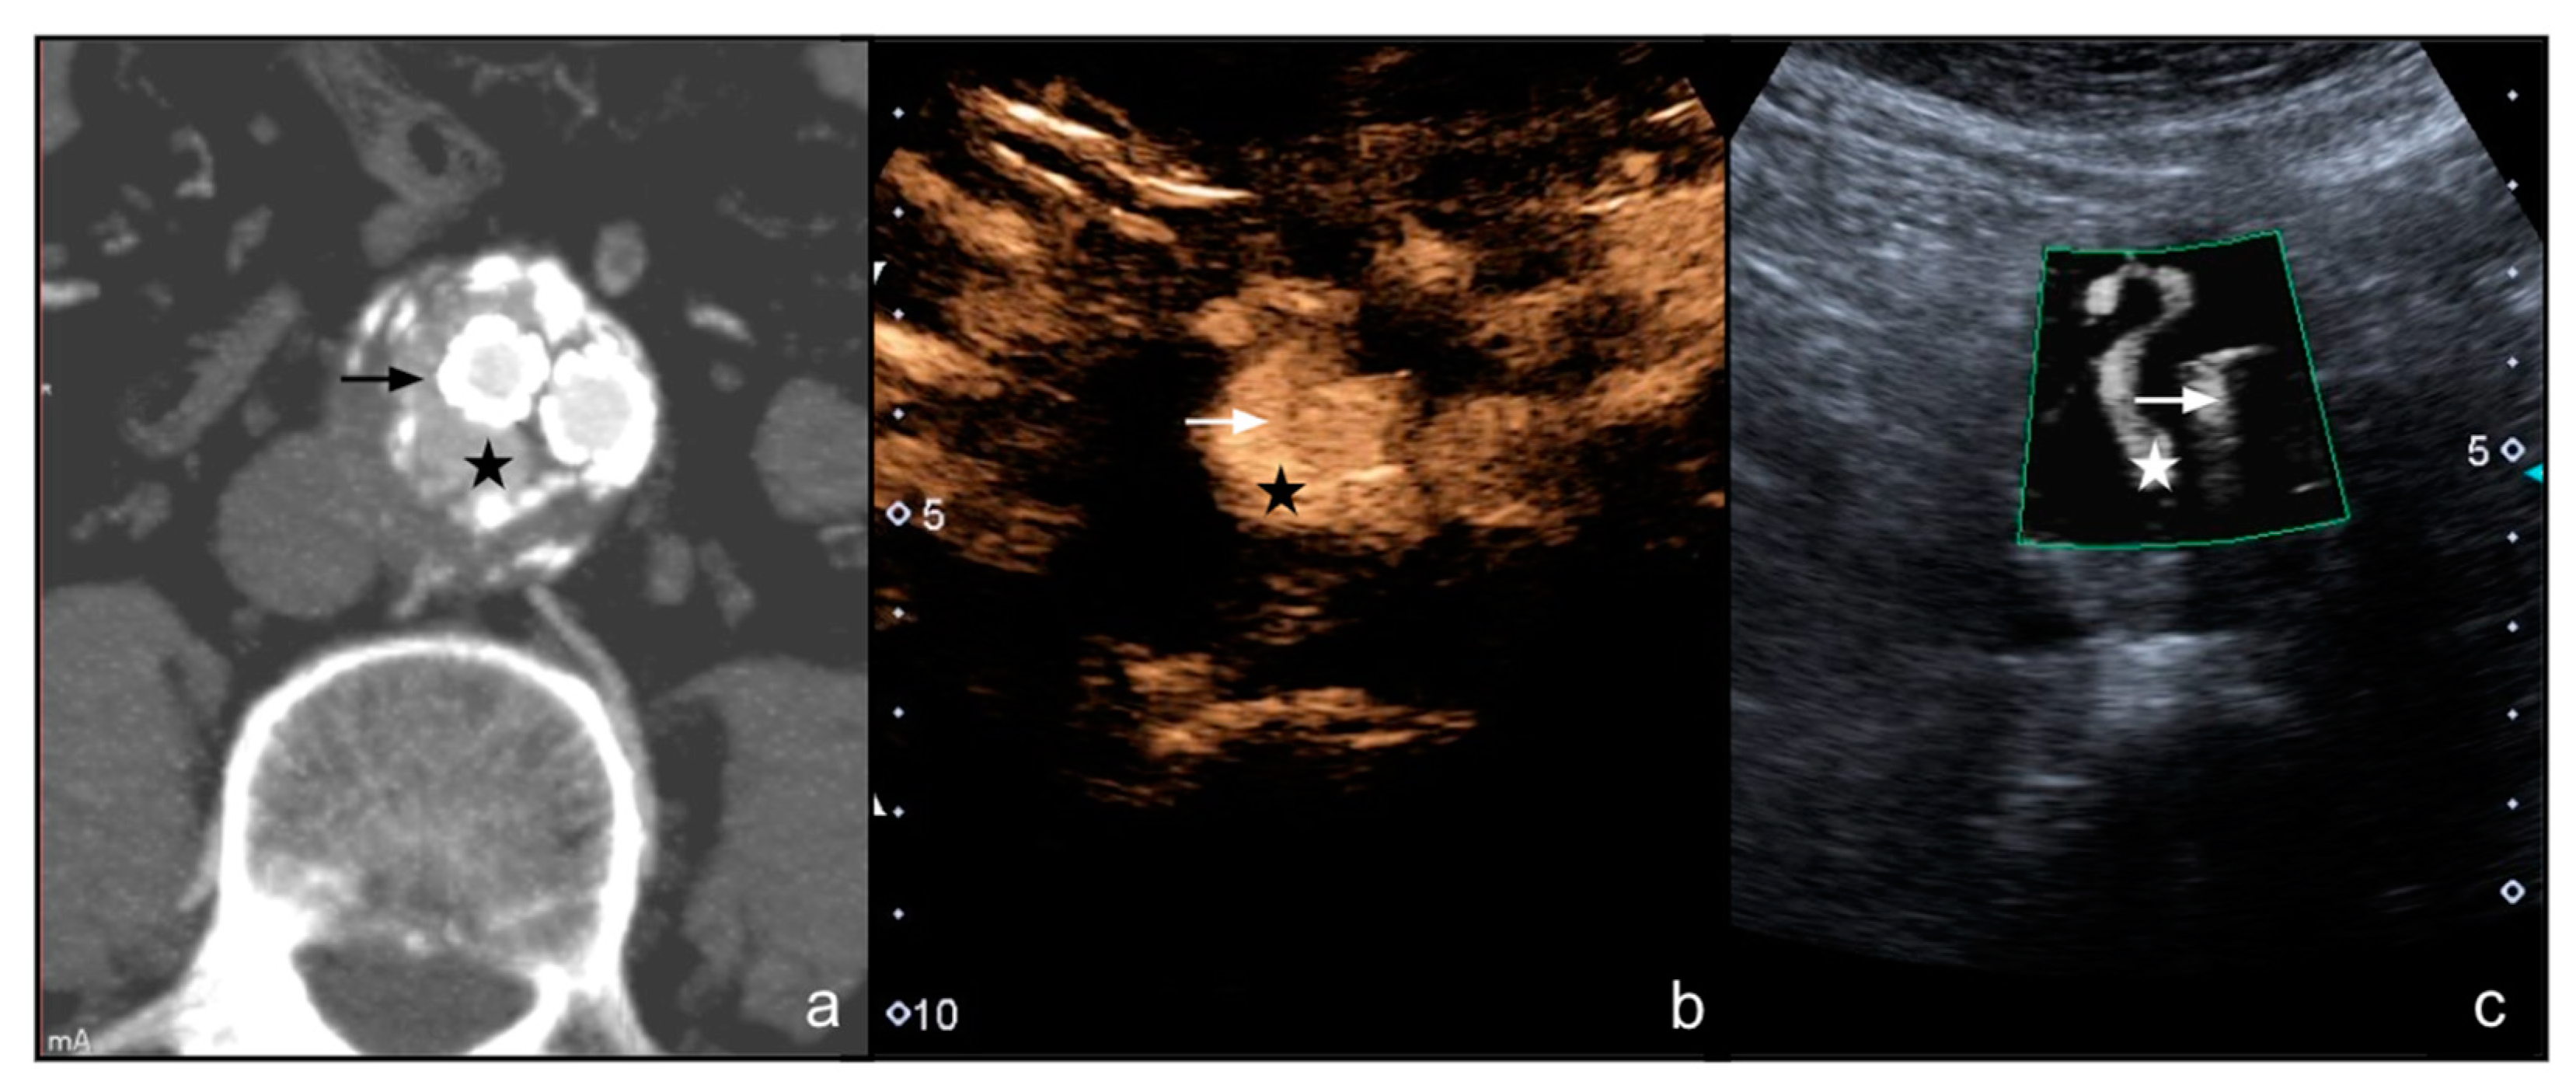

- Cantisani, V.; David, E.; Ferrari, D.; Fanelli, F.; Di Marzo, L.; Catalano, C.; Benedetto, F.; Spinelli, D.; Katsargyris, A.; Blandino, A.; et al. Color Doppler Ultrasound with Superb Microvascular Imaging Compared to Contrast-Enhanced Ultrasound and Computed Tomography Angiography to Identify and Classify Endoleaks in Patients Undergoing EVAR. Ann. Vasc. Surg. 2017, 40, 136–145. [Google Scholar] [CrossRef] [Green Version]

- Gabriel, M.; Tomczak, J.; Snoch-Ziółkiewicz, M.; Dzieciuchowicz, Ł.; Strauss, E.; Oszkinis, G. Comparison of Superb Micro-Vascular Ultrasound Imaging (SMI) and Contrast-Enhanced Ultrasound (CEUS) for Detection of Endoleaks After Endovascular Aneurysm Repair (EVAR). Am. J. Case Rep. 2016, 17, 43–46. [Google Scholar] [CrossRef] [PubMed] [Green Version]